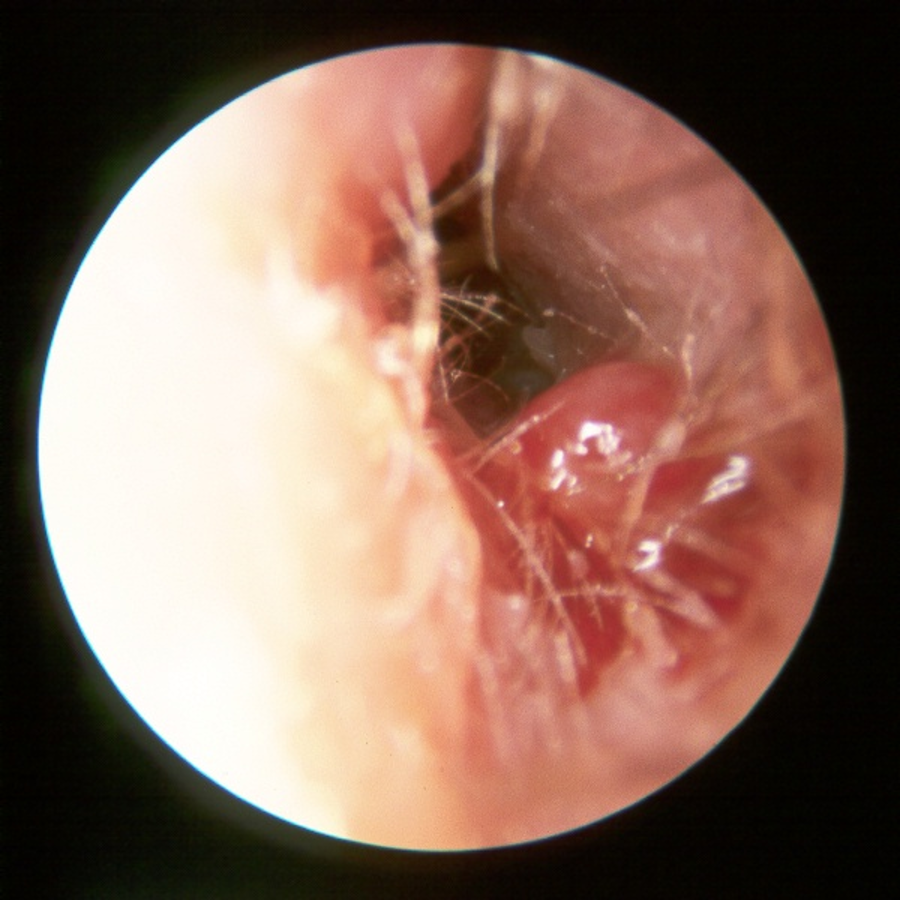

- Otorrhea/Granulation tissue